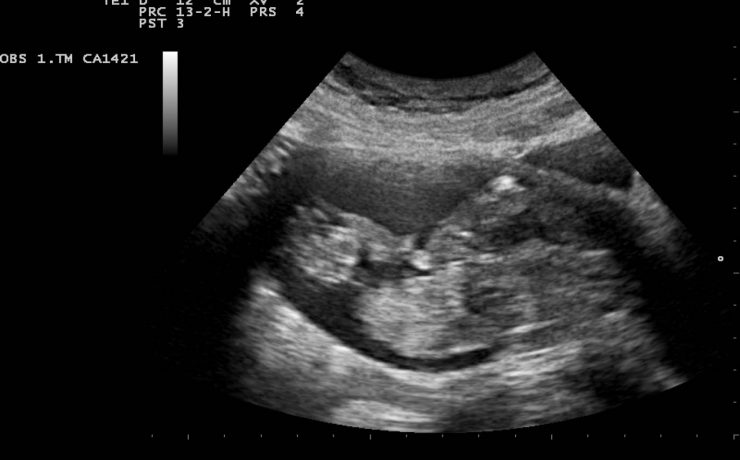

Los bultos o anormalidades en la mama generalmente se detectan por medio de un examen físico, mamografía, u otros estudios de diagnóstico por imágenes. Sin embargo, no siempre es posible detectar a través de dichos diagnósticos por imágenes si el crecimiento de los mismos es cancerígeno o benigno. Una biopsia